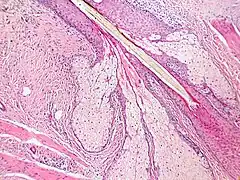

Les glandes sébacés ont une architecture acinaire (comme une grappe de raisin) et n'ont pas de lumières propre. Elles sont composés de sébocytes matures, dont la sécrétion est le résultat de leur mort par apoptose, ce qui revient à une sécrétion holocrine. Le remplacement des cellules est assuré par les cellules de la matrice reposant sur la membrane basale[5].L'annexe pilo-sébacée constituée du follicule pileux, des glandes sébacés et des muscles arrecteurs du poils, résulte d'une invagination épithéliale[4].

Multiples glandes sébacés s'abouchant à un follicule pileux.